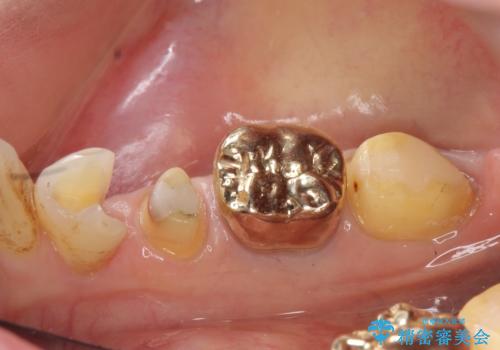

PGA(ゴールド)について

ゴールドは化学的な安定性が高いため変色や腐食がほとんどなく、アレルギーなども起こりにくい人体に優しい素材です。

また硬さも天然歯に近いため周囲の歯への影響も少なく、さらに適合もよいため虫歯の再発も少ない、とても補綴に適した材料です。